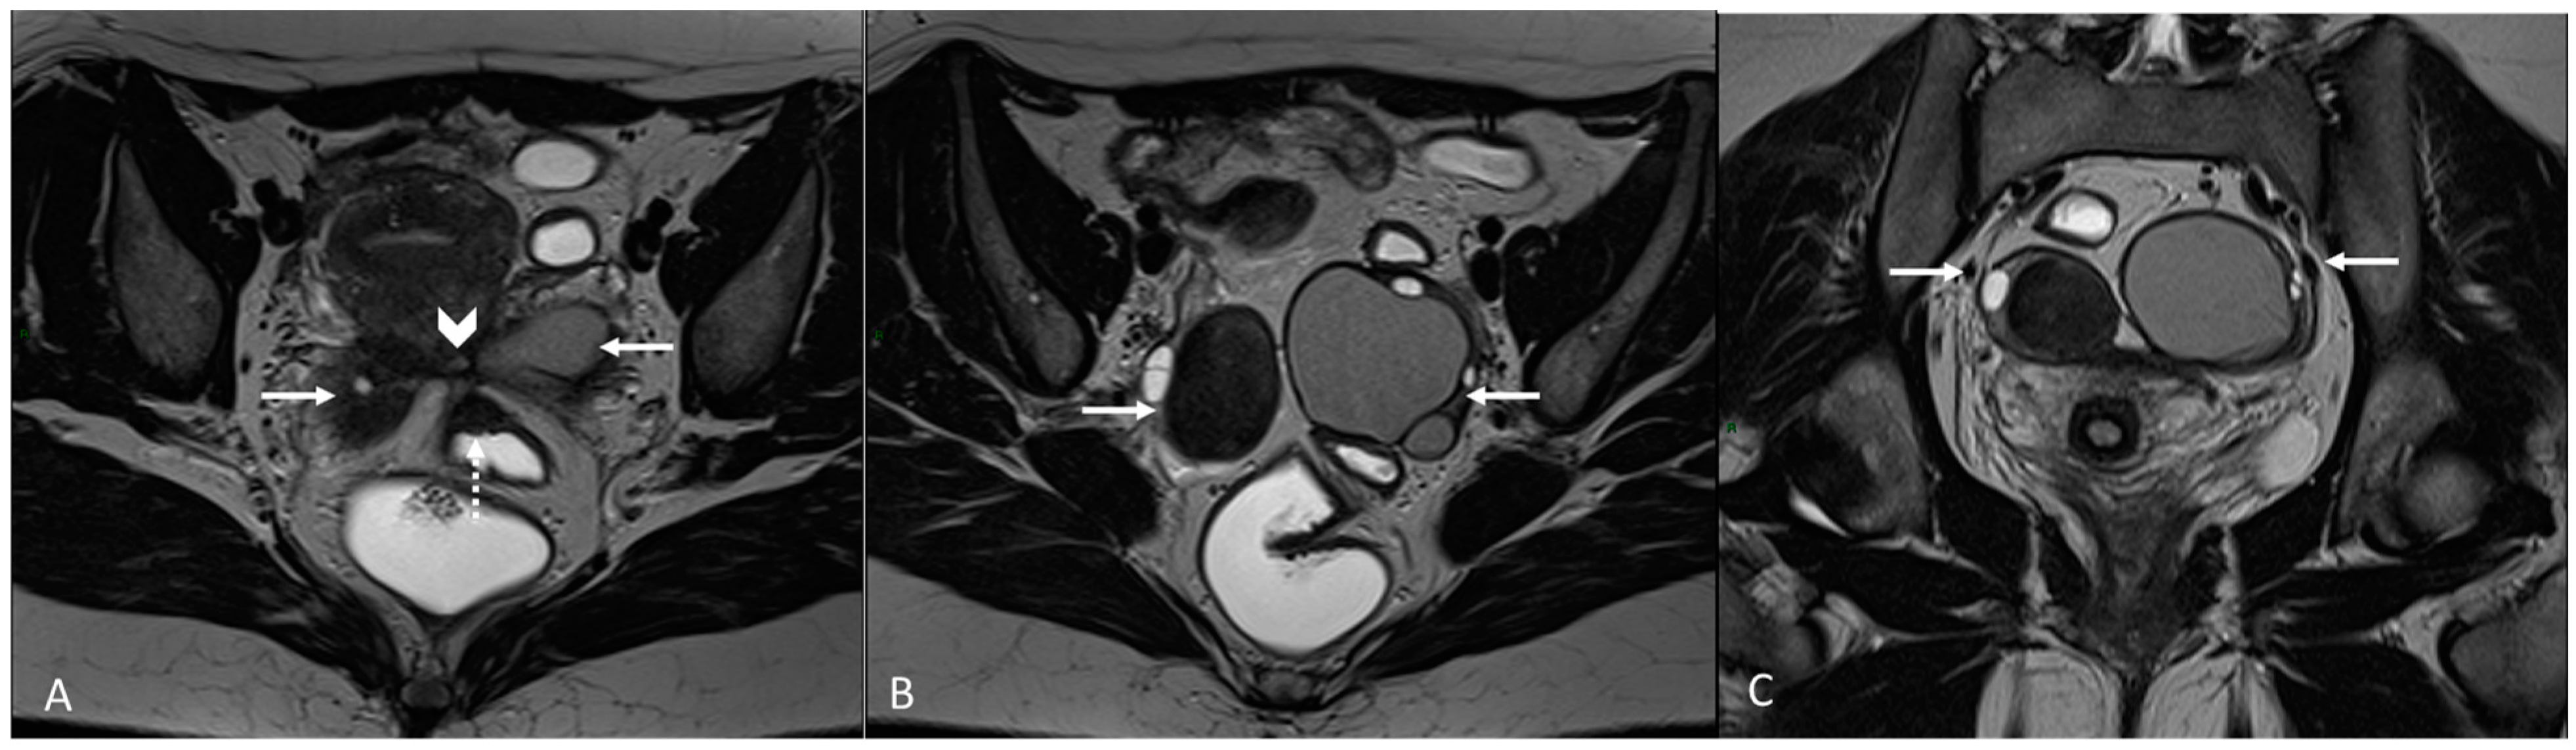

In other cases, the involvement of the round ligament can be appreciated as irregular contours with a nodular aspect [43] (Figure 2).

Figure 2.

Deep infiltrating endometriosis of the anterior and posterior compartments in 33-year-old female with dysmenorrhea, chronic pelvic pain, dyspareunia and dyschezia. (A) Sagittal T2WI. Evidence of external anterior adenomyosis and plaque of the vesico-uterine pouch (white arrow); (B) Sagittal T2WI. Retrocervical localization of DIE (white arrow); (C) Axial T2WI. Left uterosacral ligament (USL) localization (white arrowhead), plaque of vesico-uterine pouch (white arrow) with involvement of the round ligaments, particularly on the left (white dotted arrows), and adhesions with the ovaries (retraction of the broad ligaments).

The surgical approach can vary according to the proximal or distal involvement [39].

Involvement of the proximal portion of ligaments (distance less than 2 cm from the cervix) may, in some cases, be associated with thickening at the level of the torus uterinus; in such cases, it is essential to report any mass or thickening in the upper portion of the posterior cervix, as this could cause the surgeon to proceed with a laparoscopic trans-vaginal approach [7] (Figure 2, Figure 3 and Figure 4).

Figure 3.

Right uterosacral ligament localization in a 43-year-old female. The right uterosacral ligament appears thickened at uterine insertion (white arrow).

Figure 4.

Retrocervical endometriosis plaque, intestinal localization, kissing ovaries with bilateral ovarian endometriomas. (A,B) Axial T2WI; (C) Coronal T2WI. Hypointense retrocervical plaque (white arrowhead in (A)) localized in the uterine torus with involvement of the utero-sacral ligaments. Adhesions involve both ovaries with bilateral endometriomas (white arrows), which are prolapsed in a retro-uterine position and adhered to the utero-sacral ligaments and the recto-sigmoid junction. There is also an eccentric anterior parietal thickening in the recto-sigmoid junction suggestive of intestinal endometriosis lesion (white dotted arrow in (A)).